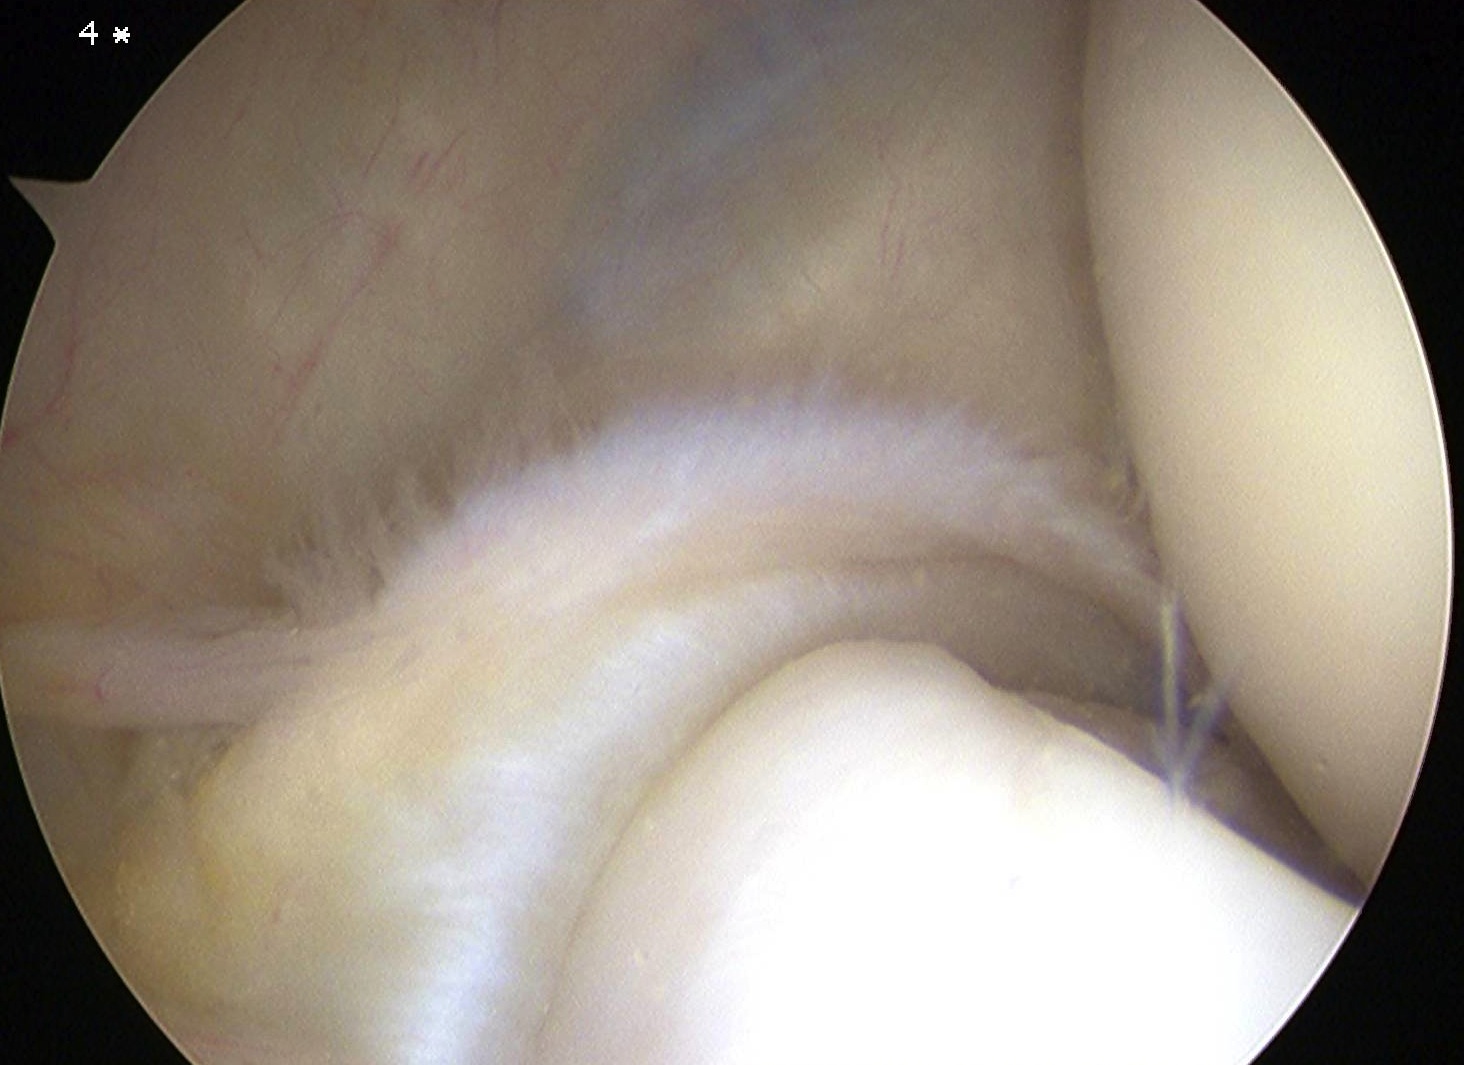

Arthroscopic tennis elbow release

Technique

Enter radiocapitellar joint

- release capsule

- release ECRB